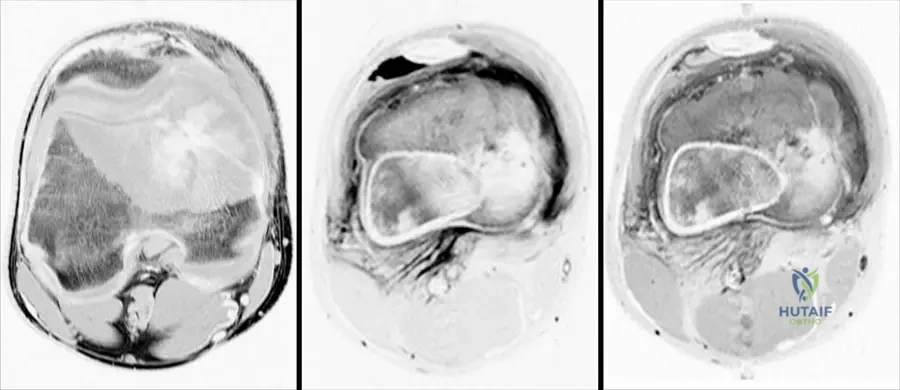

A 13-year-old male presents with a painful, rapidly growing mass in his distal femur. MRI images are obtained, as shown. These images demonstrate a large heterogeneous destructive mass in the bone with a large associated soft tissue mass. What is the most likely diagnosis based on these typical findings?

Rationale: The clinical context for Fig. 8.66 explicitly states these MRI images "show typical findings of an osteosarcoma. There is a large heterogeneous destructive mass in the bone with a large associated soft tissue mass." This is a classic presentation for osteosarcoma in this age group. Chondrosarcoma typically presents with chondroid matrix, Ewing sarcoma with a permeative pattern and onion-skin periosteal reaction, osteochondroma is a benign exostosis, and fibrous dysplasia is a benign fibrous lesion.

A 14-year-old male is diagnosed with a conventional osteosarcoma of the distal femur. Following initial radiographs and CT, the orthopedic oncologist orders an MRI of the entire femur. What is the MOST critical information this MRI is intended to provide?

Rationale: MRI is the most accurate imaging tool for determining the intraosseous and extraosseous extent of the tumor. It is also important to image the entire bone involved with osteosarcoma to evaluate for skip metastasis. This information is crucial for surgical planning and determining resection margins. Confirming osteoid matrix is done by biopsy. Assessing mineralization is better with CT. Pulmonary metastases are evaluated with chest CT. Differentiating benign from malignant is usually achieved with initial radiographs and biopsy. The image (Fig. 8.66 a–c) shows how MRI clearly delineates the extent of the mass.

A 15-year-old patient is diagnosed with a high-grade osteosarcoma of the distal femur. After initial staging, the surgical plan involves limb-salvage surgery. To ensure adequate surgical margins and rule out multifocal disease, which specific imaging technique is CRITICAL for evaluating the entire involved bone?

Rationale: The text explicitly states, "MRI is the most accurate imaging tool for determining intraosseous and extraosseous extent of the tumor. It is important to image the entire bone involved with osteosarcoma to evaluate for skip metastasis." Skip metastases are intraosseous lesions discontinuous from the primary tumor but within the same bone, and their presence dictates a wider resection. Chest CT is for pulmonary metastases. PET scan is for overall metastatic burden but less precise for intraosseous extent. Bone scan shows metabolic activity but not detailed anatomy. Plain radiographs of the contralateral limb are not relevant for skip lesions in the affected bone.

Question 35